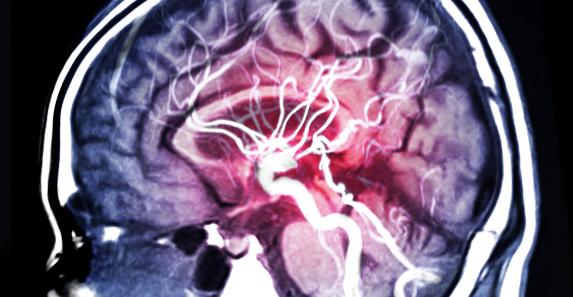

مع العلم أنه هنالك العديد من الطرق الأخرى للتنبوء بنوبات الصرع عبر التخطيط الكهربي للدماغ EEG، لكن الطريقة الجديدة تقوم بالوظيفة عن طريق عملية تعتمد على استغلال تقنيات تعلم الآلة وخوارزميات تعمل على تخطيط دقيق للدماغ وتنبوء النوبات في نفس الوقت بتتبع القنوات والنواقل الكهربية في الدماغ التي تضيء أثناء النوبة.